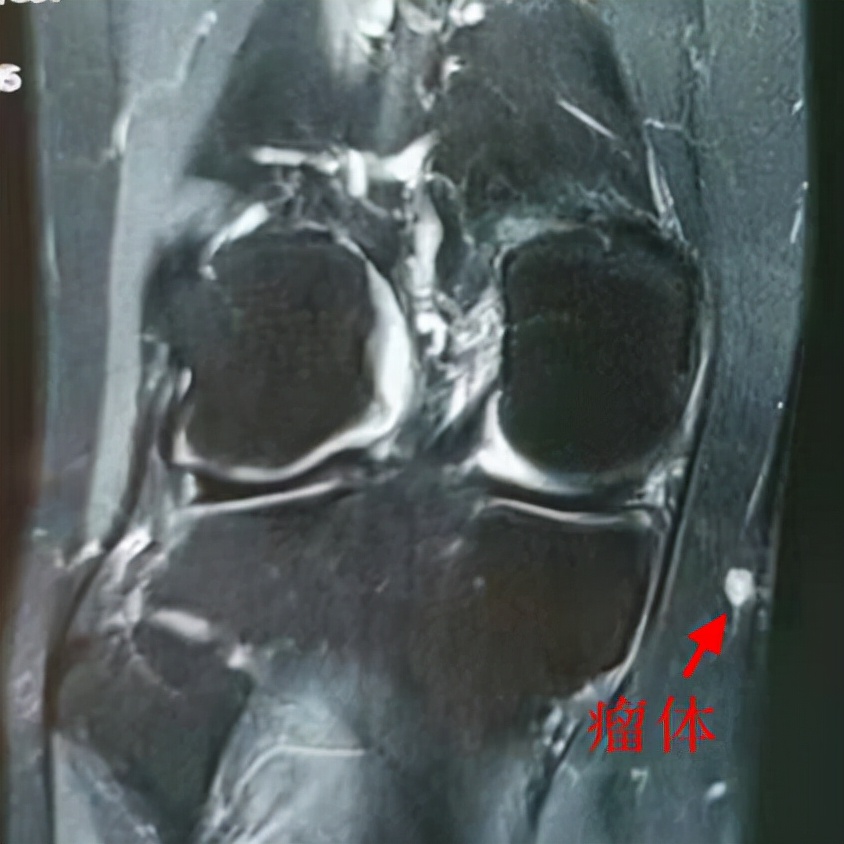

结合核磁共振的影像,张主任判断,导致王先生疼痛的是一处血管球瘤。在他的建议下,王先生接受了手术。血管球瘤切除后,患者的恢复情况良好,疼痛的部位也没有再发作。

张主任介绍,血管球瘤属于一种良性肿瘤,表现为暗红色痛性小结节。这是由细小动静脉吻合成的血管球,因为局部受外伤等因素出现增生后形成瘤体,可小至直径几毫米。瘤体内含有神经纤维,在受到外力触压或寒冷刺激时,可诱发较为剧烈的疼痛。临床上往往常见于四肢末端,如指甲下、手指及脚趾侧面等。像王先生这种生长于膝关节周围的血管球瘤并不多见。